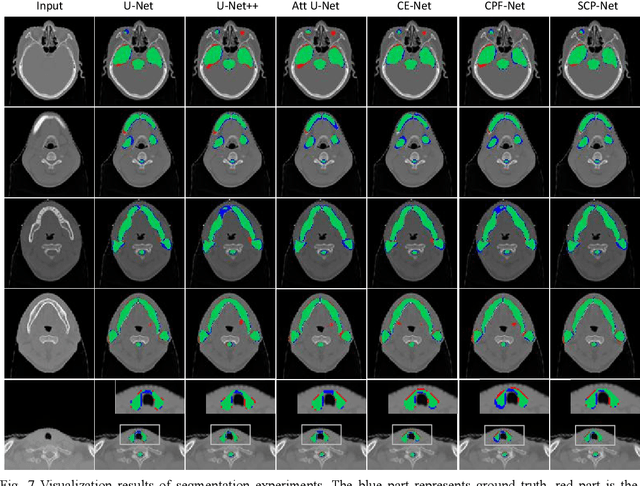

Abstract:Nasopharyngeal carcinoma (NPC) is a kind of malignant tumor. Accurate and automatic segmentation of organs at risk (OAR) of computed tomography (CT) images is clinically significant. In recent years, deep learning models represented by U-Net have been widely applied in medical image segmentation tasks, which can help doctors with reduction of workload and get accurate results more quickly. In OAR segmentation of NPC, the sizes of OAR are variable, especially, some of them are small. Traditional deep neural networks underperform during segmentation due to the lack use of global and multi-size information. This paper proposes a new SE-Connection Pyramid Network (SECP-Net). SECP-Net extracts global and multi-size information flow with se connection (SEC) modules and a pyramid structure of network for improving the segmentation performance, especially that of small organs. SECP-Net also designs an auto-context cascaded network to further improve the segmentation performance. Comparative experiments are conducted between SECP-Net and other recently methods on a dataset with CT images of head and neck. Five-fold cross validation is used to evaluate the performance based on two metrics, i.e., Dice and Jaccard similarity. Experimental results show that SECP-Net can achieve SOTA performance in this challenging task.